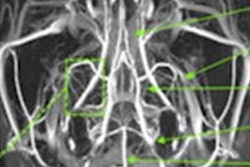

The SARS-CoV-2 virus tends to first affect a patient's respiratory system, but it can also damage the central nervous system. Physicians use electroencephalography (EEG) to identify brain injury caused by the virus, although sometimes the findings aren't conclusive. Fortunately, help is on the way: European researchers have discovered that adding MRI data to the mix of clinical information improves estimates of a patient's risk of developing COVID-19-related encephalopathy, according to a study we're highlighting in this edition's Insider Exclusive.